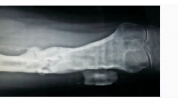

图 2 左股骨骨髓炎X线片